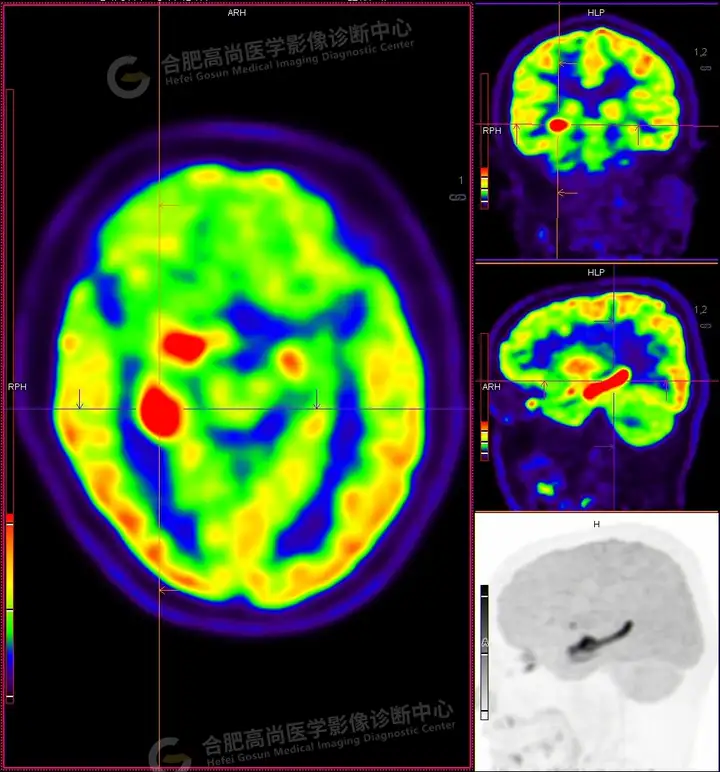

18F -FDG PET/CT检查图像:

18F -FDG PET/CT检查所见:

发作间期显像:PET显像双侧海马呈放射性摄取异常增高,以右侧明显,右侧海马SUVmax16.1、SUVavg4.4,左侧海马SUVmax7.3、SUVavg3.1(同层面额叶脑皮质SUVmax5.9、SUVavg2.3);CT示左侧海马体积较右侧似轻度缩小,左侧侧脑室颞角轻度增宽。PET显像右侧杏仁核及右侧基底节区局灶性放射性摄取异常增高,SUVmax14.1、SUVavg5.7(左侧SUVmax5.1、SUVavg3.6);CT示右侧杏仁核及右侧基底节区大小、形态正常,未见异常密度灶。

18F -FDG PET/CT检查结论:

发作间期显像:双侧海马、及右侧基底节区FDG代谢异常增高,考虑致癫灶可能大,请结合临床。